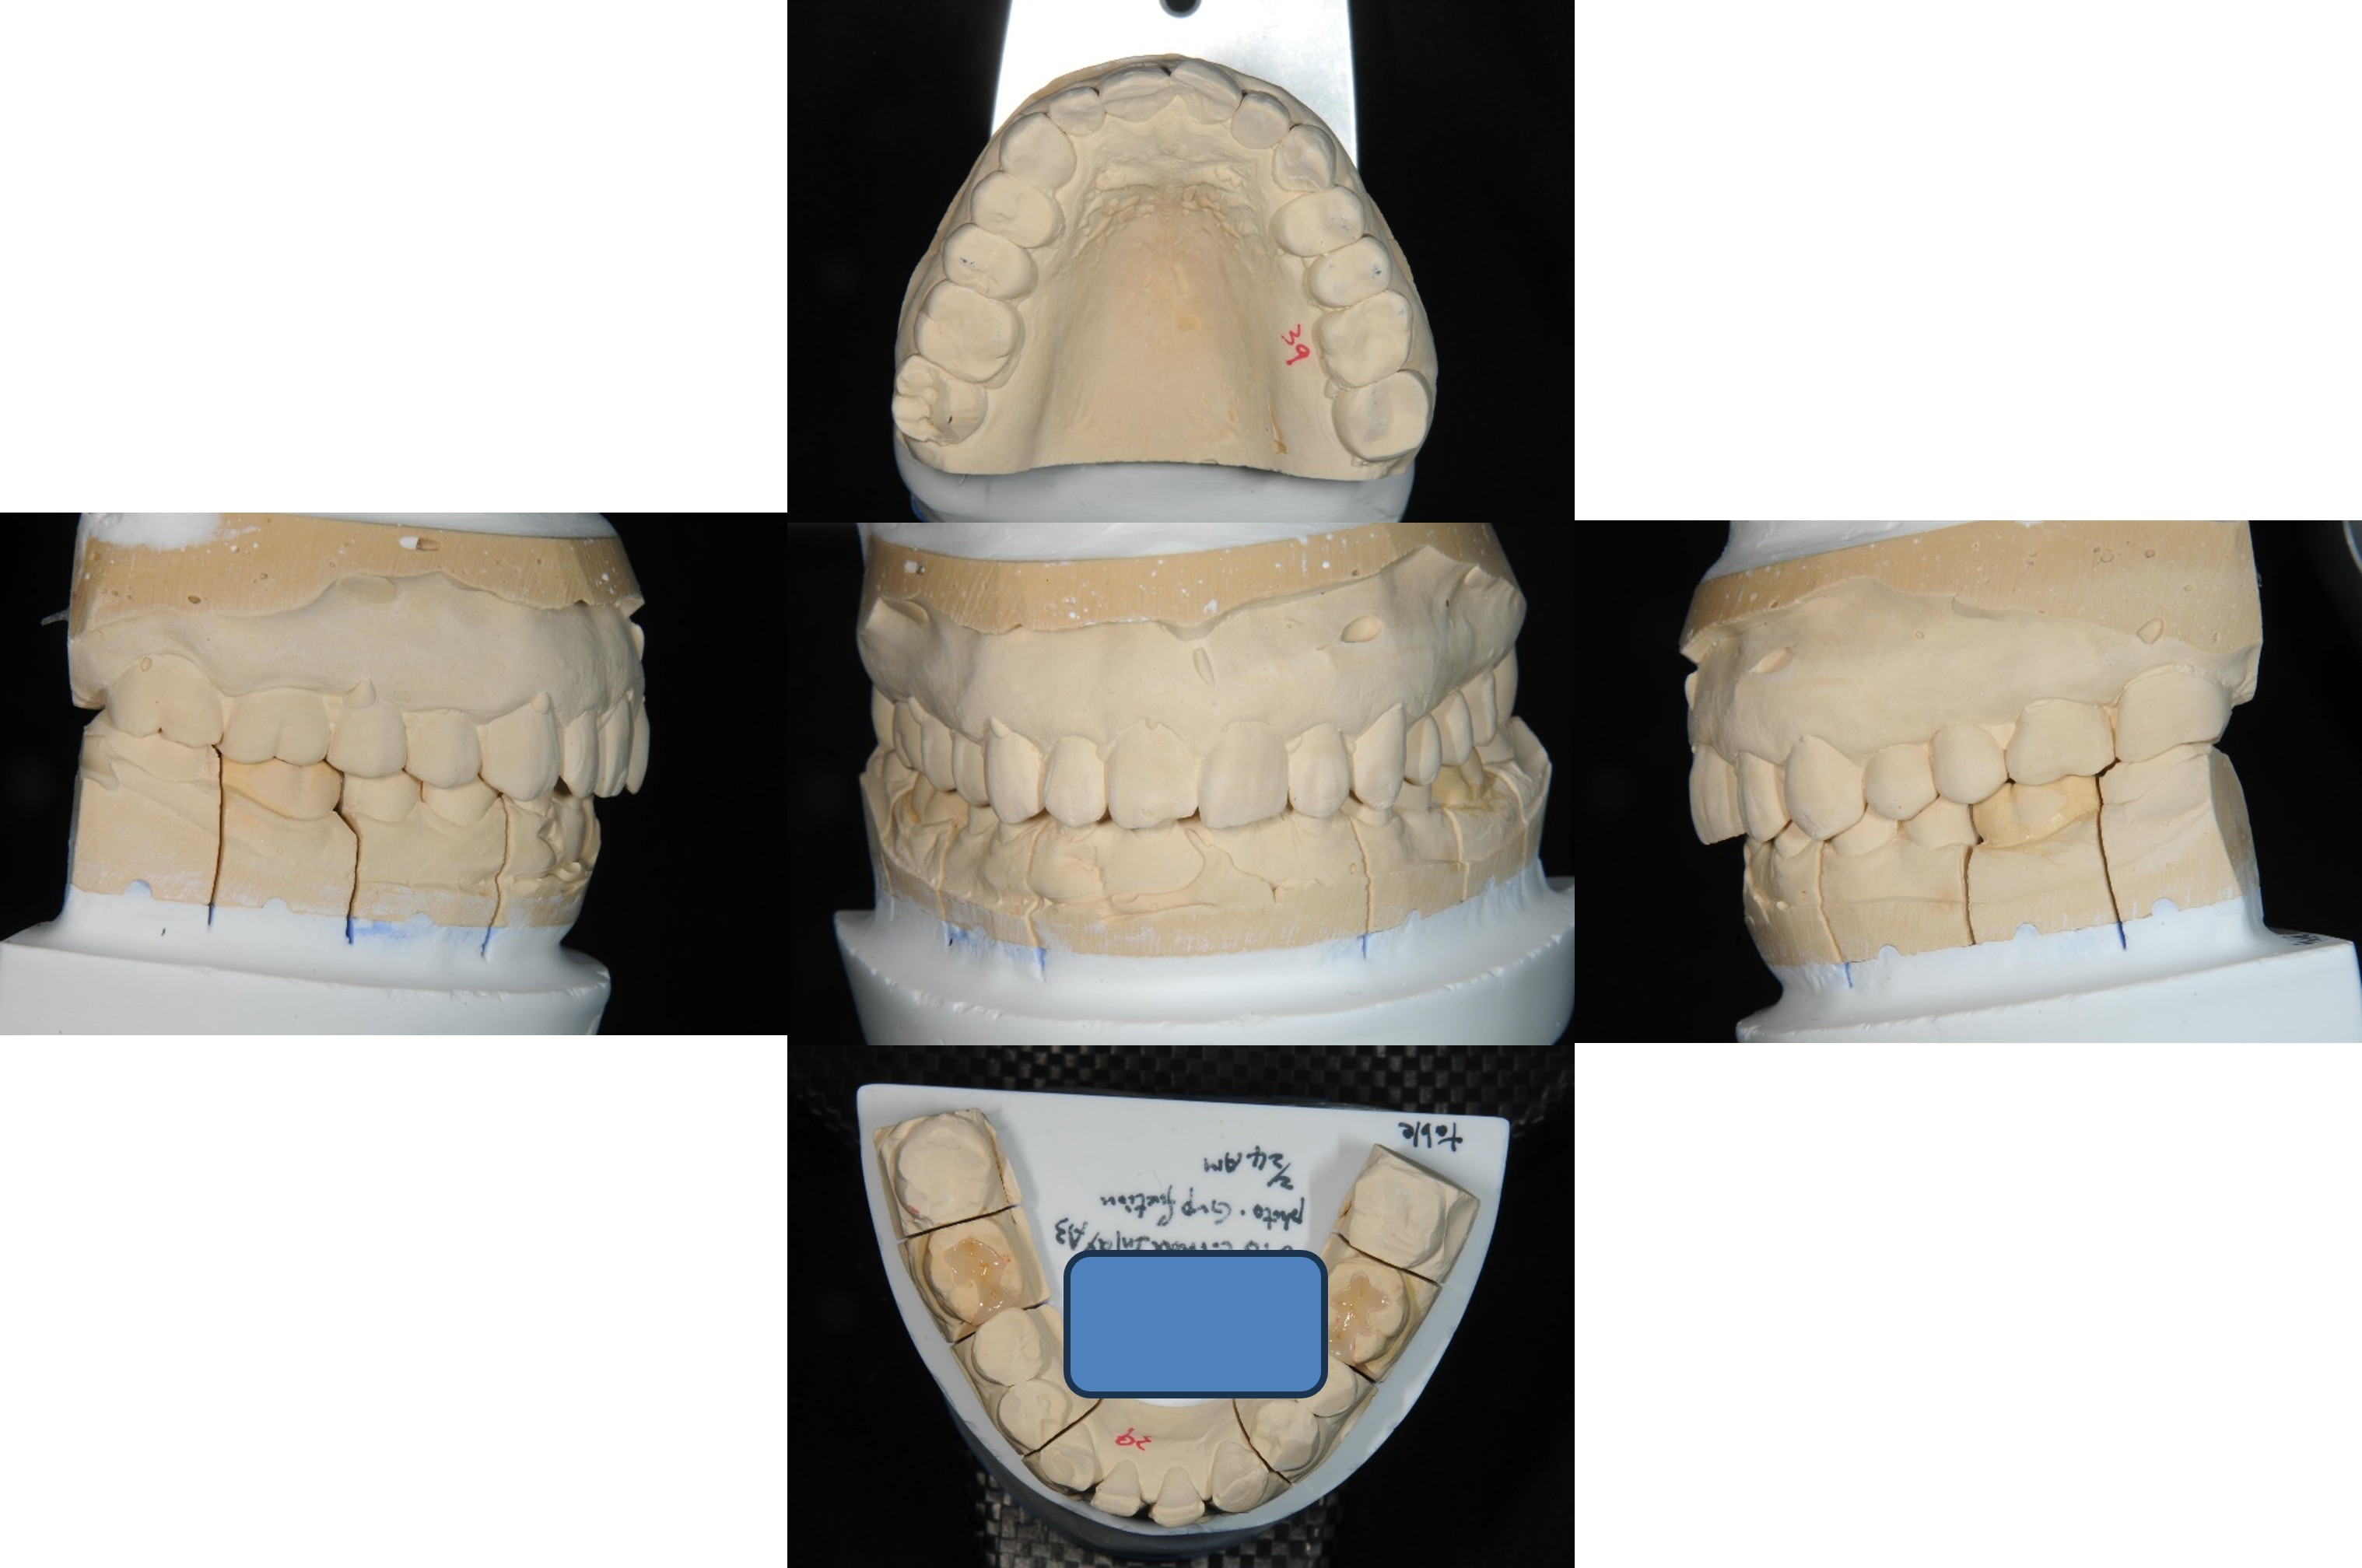

經面弓轉移,上咬合器

技師於咬合器上製作模型